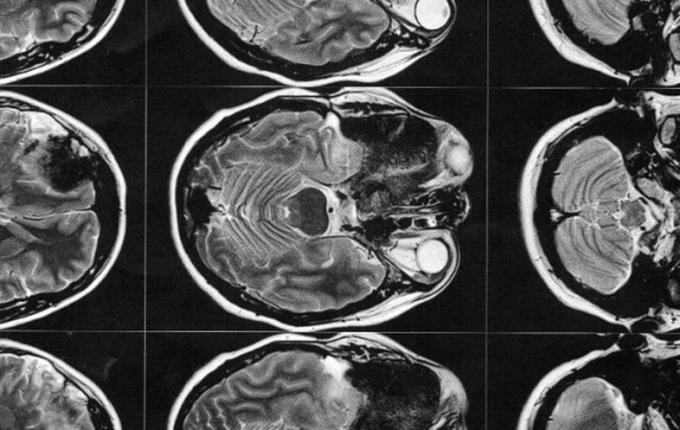

Então este médico solicitou exames de imagem (ressonância magnética e tomografia) para avaliar a situação, os quais foi constatado que o meningioma ainda está ali, e que continua empurrando o olho e se expandindo para outras áreas. Trata-se de um meningioma gigante (medindo 6 x 6,6 x 6 cm), que está localizado na placa do assoalho da fossa média e anterior.